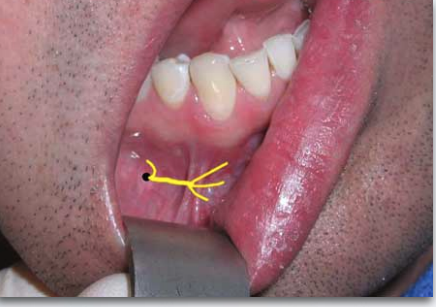

target areas for which technqieu?

AKINOSI CLOSED MOUTH TECHNIQUE

what is the proper height of insertion with AKINOSI CLOSED MOUTH TECHNIQUE?

mucogingival junction of maxillary 2nd or 3rd molar

what is the proper insertion depth with AKINOSI CLOSED MOUTH TECHNIQUE?

25 mm (measured from maxillary tuberosity)